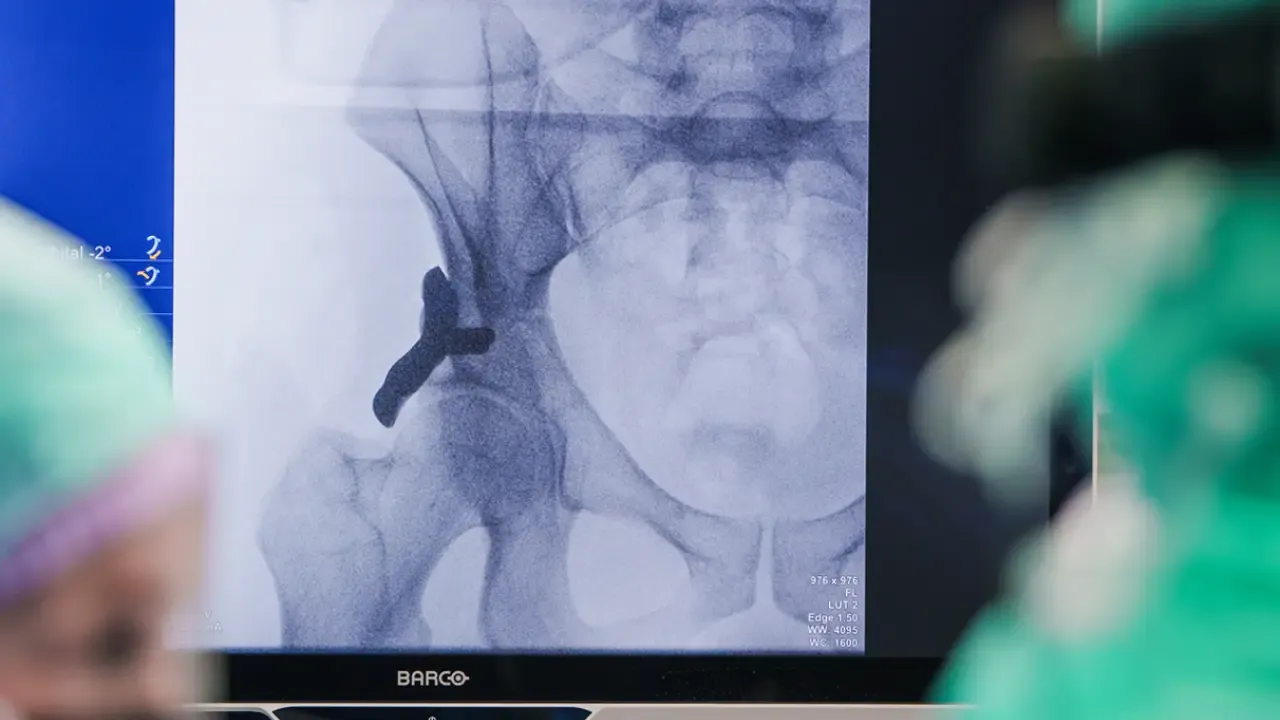

Hollanda’nın Geldrop kentinde bulunan Anna Hastanesi, tıp dünyasında bir ilke imza attı. Hastanede bir hastaya, 3D yazıcıyla üretilmiş kişiye özel bir kalça implantı yerleştirildi. Cuma günü gerçekleştirilen operasyonla uygulanan yeni teknik, gelecekte kalça displazisi bulunan hastalarda ağır cerrahi müdahalelerin yerini almayı hedefliyor.

Klasik kalça protezi ameliyatlarında eklemin tamamen değiştirilmesi gerekirken, 3D yazıcıyla üretilen yeni implant kişiye özel olarak tasarlanıyor. Bu implant, kalça yuvasının duruşunu ve eklem desteğini iyileştirerek hastanın kendi kalça eklemini mümkün olduğunca korumayı amaçlıyor. Böylece eklemdeki aşınmanın yavaşlatılması ve tam kalça protezi ihtiyacının ileri bir tarihe ertelenmesi hedefleniyor.